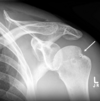

what is this

Défaut hill-sachs postéro-supérieur : trace d'une luxation antérieure qui a eu lieu